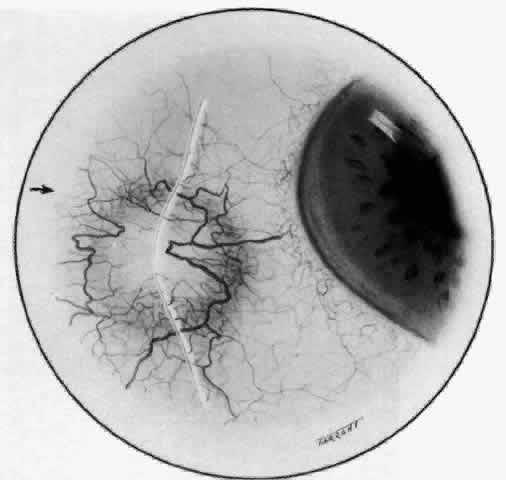

The characteristic features of necrotizing scleritis on fluorescein angiography are hypoperfusion and, eventually, nonperfusion of the vascular networks (Figs. 40 through 43).26 The initial changes are on the venous side of the capillary network; the transit time of the dye increases even if the eye is red and congested. If the disease process persists or has been present for a long time, thrombosis and permanent vaso-occlusive changes occur. These vessels (or the occluded capillary network) are bypassed by the opening of anastomotic channels. New vessels in a granuloma give rise to deep intrascleral leakage of dye (see Fig. 43). Conjunctival and episcleral involvement by the destructive change is late but is always preceded by vaso-occlusive changes that can sometimes be detected with use of the red-free light on the slit lamp (Figs. 44 and 45).

Fig. 40. Early necrotizing scleritis. There is characteristic yellow discoloration of the sclera underlying the conjunctiva at a point of necrosis. In this instance a small filament of tissue has penetrated the conjunctiva.

Fig. 41. Late stage of fluorescein angiogram adjacent to the site of necrosis in the same patient as in Figure 40. Although the eye is uniformly congested, the area near the necrosis shows vascular shutdown, whereas the rest of the conjunctiva and episclera is normally perfused.

Fig. 42. Late arterial phase of fluorescein angiogram in a patient with necrotizing scleritis. All the vessels except the main trunk and the vessels around the limbal perforating vessels are occluded and remain unperfused throughout the angiogram.

Fig. 43. Late venous phase of angiogram of a patient with necrotizing scleritis showing late deep leakage from vessels on the surface of the sclera and leakage of the capillary network at the limbus and the vessels draining it, together with poor or absent perfusion of the remaining vessels.